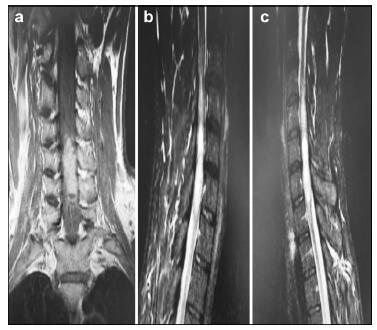

20170512093647  Figure 2 a–c. Postoperative MR images of Case 1.